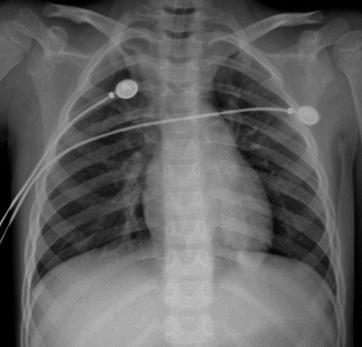

X-ray demonstrates increased, thickened, blurry, and deranged pulmonary markings, which are especially obvious at the middle and medial parts of the both middle and lower lungs. The transparency of lung fields is increased, with pulmonary emphysema as well as enlarged and thickened hilar shadow (Figs. 23.9, 23.10, 23.11, and 23.12). The severe cases are often characterized by flakes of consolidation shadows and extensive exudative lesions in the lungs. The conditions are possibly complicated by pleural effusion and pneumothorax (Figs. 23.13, 23.14, 23.15, 23.16, and 23.17).

Fig. 23.9.

Adult measles pneumonia. X-ray demonstrates flakes of ground-glass opacity with lobular distribution at the posterior segment of right upper lung lobe

Pediatric measles complicated by pneumonia and acute respiratory distress syndrome. (a) X-ray demonstrates extensive high density in both lung fields and absent pulmonary markings in both lungs. (b) By reexamination after treatment for 1 day, X-ray demonstrates multiple large flakes of shadows in both lungs and increased transparency of both lungs. (c) By reexamination after treatment for 4 days, the lesions are demonstrated to be improved. (d) By reexamination after treatment for 7 days, consolidation density is demonstrated in the lung fields of both lungs with inner bronchial shadows, and poorly defined at both lungs

Case Study 9